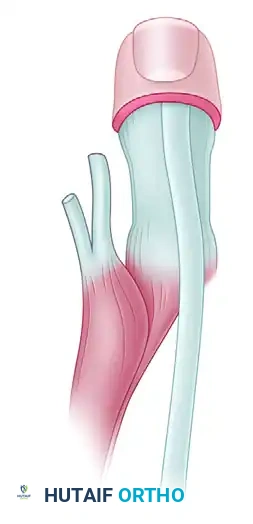

Techniques for Cleft Closure and Web Space Deepening

Closing the cleft requires careful management of the metacarpals. Bony elements that block closure should be excised sparingly; excessive removal of the central metacarpal base can weaken the transverse carpal arch and lead to recurrent clefting.

When cleft closure is combined with first web space deepening, the index ray is often transposed ulnarly to the long metacarpal position.

* Snow and Littler Technique: Involves a complex palmar flap to reconstruct the first web space while transposing the index ray.

* Miura and Komada Technique: A technically less demanding alternative that produces comparable functional results with a significantly lower risk of flap necrosis.

* Upton and Taghinia Technique: Advocates for avoiding complicated dorsal and volar flaps entirely due to the high risk of tip necrosis. Instead, they utilize a simple incision separating the glabrous from the dorsal skin surfaces.

Upton and Taghinia technique: Incisions within the cleft are placed precisely at the juncture of the glabrous and dorsal skin. A small trap-door flap is utilized for commissure lining between the ring and transposed index finger, ensuring robust vascularity.